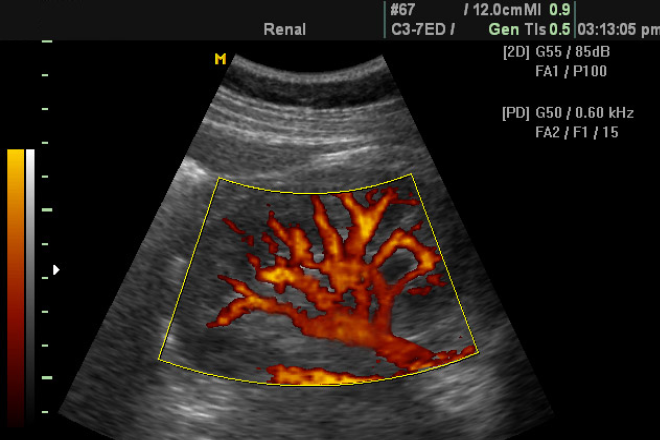

Doppler potencia: se ven coloreados los vasos, pero no se tiene en cuenta el sentido de la sangre. Es más sensible a la velocidad del fluido, pero se suelen generar algunos artefactos, como el de vibración tisular.